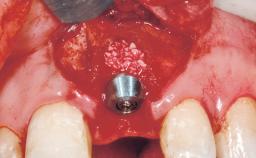

Immediate Flapless Placement of an Implant in a Maxillary Left Central Incisor Site

A 29-year-old female patient presented for treatment to replace the upper left central incisor tooth with an implant- supported restoration. The tooth had been intermittently symptomatic for the previous 12 months. The tooth had originally suffered trauma about 15 years previously. Several endodontic treatments had been performed, including an apicectomy procedure to retain the tooth. The patient was healthy and a non-smoker. She had reasonable expectations in regard to esthetic outcomes and the risk of marginal tissue recession following treatment. At medium smile, the gingival margins of the upper teeth were visible, with a display of 3 to 4 mm of the gingival margins. Gingival recession of tooth 21 and a discrepancy in the gingival levels between teeth 11 and 21 was observable during normal speech and smile.

Placement Protocol Immediate implant placement

Socket Integrity Damage to one or more bone walls

Bone Volume Damage to one or more socket walls

Esthetic Risk Medium

Risk of Complications High